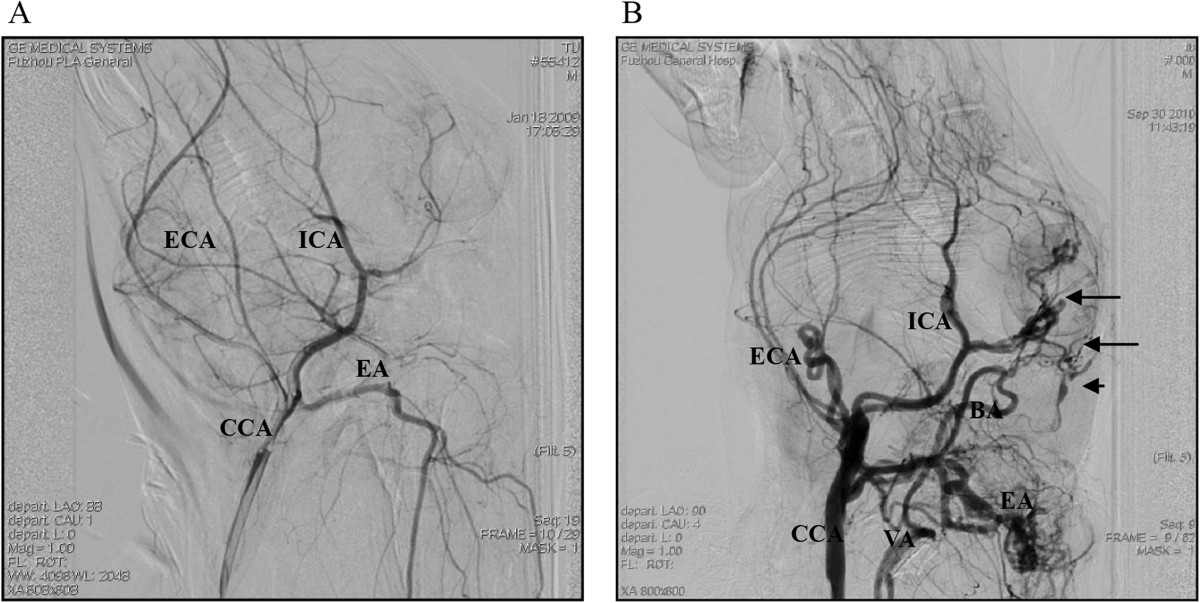

背景:硬脑膜动静脉瘘的形成原因尚未明确。本研究旨在探讨兔颅内静脉高压致硬脑膜动静脉瘘形成的机制。结果:采用兔模型,右侧颈总动脉与面后静脉加上对侧颈外静脉结扎后的端对端和端侧吻合,可产生颅内静脉高压致硬脑膜动静脉瘘的形成。相比在1周,2周,3周,90天后动静脉瘘的形成,在1 周和2周的血管内皮生长因子的表达水平与显著高于对照组,3周和90天组。1周组与对照组,2周、3周和90天组相比,缺氧诱导因子-1α表达明显升高。Western印迹结果显示,1周组血管内皮生长因子表达水平最高。各组血管内皮生长因子表达水平差异有统计学意义。结论:兔模型的实验结果表明,高颅内静脉压是硬脑膜动静脉瘘形成的关键。脑灌注压力不足引起的脑缺血在颅内静脉压增高导致缺氧诱导因子-1α表达增加,血管内皮生长因子表达增加的过程中起关键作用。关键词:硬脑膜动静脉瘘 兔模型 颅内静脉高压 缺氧诱导因子-1 血管内皮生长因子背景:硬脑膜动静脉瘘(DAVF)是一种异常的连接动脉和脑膜静脉或硬膜静脉窦或皮质静脉。是一种颅内血管畸形。硬脑膜动静脉瘘约占颅内血管畸形的10-15%,幕上动静脉畸形6%和幕下动静脉畸形的35%。硬脑膜动静脉瘘可发生在任何部位,但这些血管畸形最常见于海绵窦、横窦、乙状窦及上矢状窦(SSS)。DAVF的治疗形式主要是血管内栓塞治疗。DAVF的原因尚未明确。有先天和后天的原因。有一种观点认为,硬脑膜动静脉瘘是一种颅内动静脉畸形和硬脑膜血管异常引起的先天性疾病。已经有很多临床试验表明,硬脑膜动静脉瘘的形成可能是造成脑外伤,静脉窦炎症、静脉窦血栓形成、颅内肿瘤、脑手术、高凝状态、血液分子异常等,DAVF是一种获得性血管疾病。认为获得性DAVF是由于DAVF和静脉窦血栓形成之间的关系较为密切。许多研究者建立了大鼠静脉窦高压模型颈总动脉颈外静脉吻合(CCA-EJV)方法。1)高静脉窦压力可能诱发DAVF;2)自动排除大静脉窦压力后DAVF消失;3)术后28 d,高压组静脉压明显升高;4)静脉窦血栓形成是高静脉窦压的危险因素。有利于DAVF形成关键点是颅内静脉窦压增高。有两种理论解释:一是开放的"生理动静脉吻合",另一种是"血管内皮生长因子诱导的硬脑膜血管生成。"本研究的目的是通过使用兔模型诱导形成的高颅内静脉压调查更详细的DAVF形成机制。本研究采用cca-pfv吻合产生高颅内静脉压模型,成功诱导DAVF形成,首次发现缺氧诱导因子-1α(HIF-1α)和血管内皮生长因子在兔模型中的表达。方法:实验动物:该研究经过福利伦理委员会的批准。100只日本大耳雄兔(体重2.0~2.5 kg)。麻醉:通过注入1%戊巴比妥钠(25毫克/公斤)到耳静脉(EV)进行麻醉诱导,包括动静脉吻合,颈动脉放置导管,收获标本。百分之一戊巴比妥钠经导管注入颈动脉进行脑血管造影。动物准备:实验动物分组:五十只雄性日本长耳兔随机分为五组,A -E. A组(对照组)假手术(n = 10)。B组实行右侧颈总动脉(CCA)-面后静脉(PFV)端端吻合术(EEA) (n = 10)。C组实行右侧颈总动脉(CCA)-面后静脉(PFV)加左侧颈外静脉(EJV)(n = 10)。D组实行右侧颈总动脉-面后静脉cca-pfv端侧吻合(ESA)(n = 10)。E组实行右侧右侧颈总动脉-面后静脉cca-pfv端侧吻合加左侧颈外静脉(EJV)结扎(n = 10)。术后7、14、90天各组随机抽取2只兔,墨汁灌注后计数硬脑膜微血管数。术后90天,每组选取4只兔进行数字减影心血管造影术冰观察DAVF的形成。另取五十只日本大耳白兔随机分为五组,A -E组。A组(对照组)假手术(n = 10)。B-E组(n = 40)实行右侧颈总动脉(CCA)-面后静脉(PFV)端端吻合术(EEA)加左侧颈外静脉(EJV)结扎。在B、C、D、E组(n=10)分别于术后1周、2周、三周、术后第90天取标本进行进一步免疫组化(每组6只)和蛋白印迹分析(每组4只)。模型制备:手术前动物禁食10小时,不限制饮水。1%戊巴比妥钠(25毫克/千克)被注入到左耳静脉EV。麻醉后将兔固定在手术台上。颈部去毛并用碘伏消毒,皮肤切口在颈部。以下步骤在显微镜下进行。1、 A组:解剖分离出双侧颈外静脉。近端是在前、后面部静脉和颈外静脉交叉前部1cm结扎,远端是前、后面部静脉和颈外静脉交叉后部1cm结扎。暴露右侧颈动脉三角,钝性分离2厘米的CCA。24 #静脉(IV)导管分别穿刺入面后静脉(PFV)和CCA,并与侵入式压力测量仪器相连,测量CCA和PFV实验压力。局部应用少量青霉素后缝合切口。2、 B组分离出双侧颈外静脉和右侧CCA(长度等于假手术组)。测定正常的动脉压和PFV压力。右侧颈外静脉的前端被结扎(前面部静脉和后前面部静脉和颈外静脉的交界处0.5厘米)。前面静脉远端(AFV)也被结扎。用血管夹夹住PFV,面后静脉(PFV)与颈外静脉交叉处前约3cm处切断。CCA的近端被截断,远端被结扎和切断,血管的内腔用1毫克/毫升肝素/生理盐水溶液洗涤。CCA和PFA的残余部分用亚甲蓝染色,然后用1毫克/毫升肝素/生理盐水洗涤。端到端的CCA和PFV吻合用9-0缝线进行。吻合术后进行吻合口通畅验证。测量吻合后的PFV压力,和切口使用少量青霉素后缝合伤口。3、 C组 分离出右侧CCA、EJV和左侧EJV。左侧EJV用4-0缝合结扎。其他操作同B组。4、 D组 分离出双侧颈外静脉与右侧CCA(分离长度与假手术组相同)。测定正常的动脉压和PFV压力。对右侧EJV的前段和AFV的远端进行结扎。夹住PFV,在PFV和EJV交叉处约3mm的地方切断。血管腔用1毫克/毫升肝素/生理盐水洗涤。使用两个血管夹来夹住CCA,两个剪辑之间的距离是约1.5厘米。用微剪刀沿容器壁切入,切口长度为管径的1.5倍长。血管的内腔用1毫克/毫升肝素/生理盐水溶液洗涤。CCA的切口和PFV残段用亚甲基蓝染色并用1毫克/毫升/肝素生理盐水溶液冲洗。颈总动脉与PFV之间用9-0缝线进行端侧吻合。对吻合口通畅进行验证。测量吻合后的PFV压力,切口使用少量青霉素后缝合。5、 E组:分离出右侧CCA、EJV和左侧EJV。左侧EJV用4-0缝线结扎。其他操作同D组。测量压力:将5组共50只兔的右侧颈总动脉(CCA)剥离出来,并测量CCA压力。颈总动脉血压测量:剥离CCA约2cm,24#IV导管从尾部插入,用血管夹固定,并连接无创血压测量装置。在心脏水平,压力调整到零。在读数稳定后,进行拍摄和记录。面后静脉压力测量:将5组共50只兔的面后静脉(PFV)剥离出来,并测量PFV压力。剥离右侧颈外静脉、面前静脉和面后静脉的总长度约2cm。将24#IV导管通过静脉瓣膜插入PFV,固定后与侵入式压力测量仪相连。在心脏水平,压力调整到零。在读数稳定后,进行拍摄和记录。吻合术后面部静脉压力的测量:B-E组的40只兔子,在测量PFV压力和剖杀之前验证cca-pfv吻合术后吻合口通畅。将24#IV导管通过静脉瓣膜插入PFV,固定后与侵入式压力测量仪相连。在心脏水平,压力调整到零。在读数稳定后,进行拍摄和记录。墨汁灌注:从B-E组做完CCA-PFV吻合术后的第7、14、90天和A组每组选取2只兔进行投颈部墨汁灌注。计数硬脑膜微血管密度。DSA检查:术后90天,从五组中每组选取4只兔头颈部进行DSA检查。具体程序如下:导管放置在颈动脉:经过耳静脉注射1%戊巴比妥钠(25mg/kg)麻醉动物,将家兔置于仰卧位并固定在手术台。沿原颈切口进行解剖。右动静脉吻合部位仔细解剖。周围有许多新的静脉形成。经验证吻合口通畅后,测量术后面部静脉压。固定吻合部位。剥离左CCA,并放置24G静脉导管。导管充满1毫克/毫升肝素,闭合颈部切口。获取DSA图像:通过CCA注射1%戊巴比妥钠,将家兔置于仰卧位并固定于DSA桌。调整机器的位置,iohexol-300是通过放置在CCA造影导管注射(2ml/s,3ml)。拍摄前后X线片。免疫组化:从对照组、7天、14天、21天和90天组,每组6只兔采集枕叶皮质和硬脑膜标本进行HIF-1α和VEGF免疫组化。枕叶皮层的选择,因为该区首先受吻合影响产生颅内高压且其能较方便地进行试验。将免疫组化切片组织,福尔马林固定后石蜡包埋,切片用苏木精和曙红(HE)染色。组织切片与下列主要抗体孵育:血管内皮生长因子(VEGF)(C)(1∶100),缺氧诱导因子- 1α(1∶200)4°C孵育过夜。然后用辣根过氧化物酶标记小鼠抗兔二抗体孵育(1:1000)。免疫组织化学分析用的3,3'- Diaminobenzidine(DAB)方法进行。所有标本在倒置显微镜和Olympus BX51照相系统下观察。百分比为阳性细胞数目除以总细胞数。用于表达水平分配数值的标准如下:-=0% ,+ = > 0% - 25%,+ +=26% - 50%,+ + +=51% - 75%,+ + + + = > 75%。Western印迹法:从对照组、7天、14天、21天和90天组,每组4只兔采集枕叶皮质和硬脑膜标本进行免疫印迹。用RIPA缓冲液裂解标本,由Bradford法测定蛋白质提取物的浓度。40μg总蛋白进行SDS-PAGE电泳,转移到10% PVDF膜,在含0.1%吐温20和5%脱脂奶粉的TBS溶液中孵育。然后膜用特异性血管内皮生长因子VEGF(C-1)一抗(1:200),HIF-1α一抗(1:200),和α微管蛋白(分子量为52 kDa,1:3000)在4°C孵育过夜。膜用辣根过氧化物酶标记的鼠抗兔抗体孵育(1:1000)。使用增强的化学发光辣根过氧化物酶底物观察免疫反应带。结果代表三个独立的实验。定量分析是由GE图像扫描仪Quantity One软件进行。结果:B组和C组动物术后均存活。由于颅内静脉压过高,D组和E组各2只兔术后3 d内死亡。吻合口通畅率B组的为80%,C组为90%,D组为60%,E组为50%。围手术期血压:术后B-E组吻合口通畅的频率无显著差异。假手术组(A组)术后静脉血压与基线比较差异无统计学意义。B-E组动物手术后和处死前,静脉压力同基线相比显著增加。术后及处死前与对照组比较,术后静脉血压明显升高。B组和C组动物的静脉血压明显高于D组和E组。B组与C组、D组与E组间差异无统计学意义。脑墨汁灌注:对硬脑膜血管微血管由凸矢状窦宽2毫米和3毫米以上的横窦进行观察和比较。硬脑膜毛细血管计数为微血管/每平方毫米数。对照组硬脑膜微血管计数为12±2平方毫米,术后14天计数为15±2平方毫米,略有增加。90天后,脑膜微血管计数明显增加, B,C,D,和E组分别为36±4平方毫米,39±5平方毫米,33±3平方毫米,35±4平方毫米。DSA检查:手术后90天A-E组每组抽取4只进行 DSA检查。动脉期DSA图像如图4所示,静脉期如图5所示。在A组,血管通畅,无异常的血管,血液循环的时间约为11-15 S。在B,C,D和E组,耳朵和眼睛区域观察到血管迂曲、硬脑膜动静脉瘘和AVF。在一些动物中,观察到两个或两个以上的动静脉瘘。在16只兔中观察到22例动静脉瘘。其中,7例为DAVFs,因此DAVF形成率为43.75%(7 / 16)。DAVFs主要位于SSS、海绵窦、横窦。DAVFs通过SSS、横窦、面后静脉被排出;眼睛动静脉瘘经前面部静脉引流;耳动静脉瘘镜面后静脉引流,颈动静脉瘘通过面后静脉引流。在B,C,D和E组循环时间延长(大约32-40S)。静脉期的循环时间明显延长,而在动脉期则没有明显延长(约5 s)。免疫组化法检测VEGF和HIF-1α的表达水平:1周和2周组的枕叶皮层和血管内皮细胞VEGF表达显著高于对照组、3周和90天组。与对照组相比,2周组动物SSS中VEGF表达水平明显升高。与对照组和2周、3周、90天组比较,1周组在枕叶皮质、软脑膜血管及SSS中均有较高的HIF-1α表达。Western blot分析VEGF和HIF-1α的表达水平:枕叶硬脑膜VEGF表达水平和枕叶皮质及SSS区HIF-1α表达水平相似。表达峰值出现在1周,其次是2周、3周、第90天和对照组。枕叶硬脑膜VEGF表达在对照组,1周,2周,3周,和90天的平均表达水平分别为10.1,27.2,34.1,16.9和11.8。枕叶皮质HIF-1α在对照组,1周,2周,3周,和90天的平均表达水平分别为9.1,35.6,24.7,20.5,10.1。SSS区HIF-1α在对照组,1周,2周,3周,和90天的平均表达水平分别为9.4, 35.6, 26.7, 17.7, 10.6。两组间比较均有统计学意义。结论:动物模型实验结果表明,颅内高压是DAVF形成的关键因素。脑缺血引起的脑灌注压缺乏在这个过程中起着关键作用,颅内静脉压增高导致HIF-1α表达增加,VEGF表达增加。